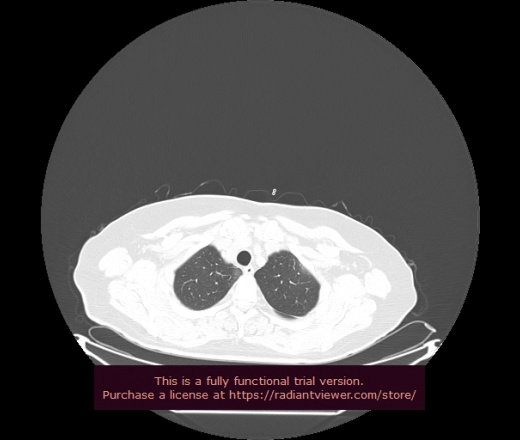

Уважаемые коллеги, если имеется интерес, сможете ли Вы спрогнозировать дальнейшее +-одинаковое течение процесса у 4 данных разных пациентов? Зацепиться где-то можно очень просто, где-то нельзя.